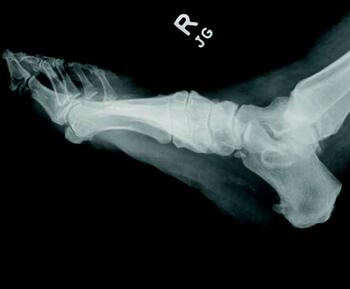

Charcot neuroarthropathy is a tissue-destructive process of the musculoskeletal system in patients with neuropathy.6-9 Most commonly affecting the foot and ankle, Charcot develops from repetitive trauma to an insensate foot. Historically, two theories describe the etiology of Charcot neuroarthropathy: the neurovascular theory; and the neurotraumatic theory. The neurovascular theory proposes that altered autonomics in patients with neuropathy leads to arteriovenous shunting and increased arterial flow, precipitating amplified osteoclastic activity and subsequent bone resorption and fracturing.10-11 The neurotraumatic theory suggests unrecognized trauma in neuropathic patients leads to repetitive injury and subsequent breakdown.12

Regardless of the cause, an acute Charcot foot is a hyperinflammatory event in the setting of immune dysregulation. Jeffcoate and colleagues hypothesized that Charcot foot developed due to the release of pro-inflammatory cytokines in an amplified immunologic response to trauma.12 They proposed a post-traumatic pathway that resulted in increased expression of TNF-α and IL-1ϐ. These cytokines induce increased expression of RANKL, which activates NF-κϐ (a transcription factor), mobilizing osteoclasts for osteolysis. Such a process would be a healthy response to injury, but in the setting of neuropathy, the injured site may sustain repetitive insults. Perhaps these repetitive insults manifest immune dysregulation, leading to an uncontrolled hyperinflammatory state.12-13 There is limited research to support this elegant theory, but there is acceptance of the proposed pathway as the most likely mechanism driving Charcot collapse.

Management of the acute Charcot foot involves management of any present ulceration or infection and aggressive offloading through immobilization to prevent progression of deformity and amplification of the inflammatory cycle.16-17 There is some early evidence to suggest using immunomodulators such as TNF-ɑ inhibitors in the management of acute Charcot foot.18 Bisphosphonates are occasionally part of the treatment for the acute Charcot foot with mixed results.19 Surgical management of the acute Charcot foot is rarely indicated as surgical trauma may worsen the inflammatory cascade, resulting in even more bone resorption.

Acute Charcot arthropathy and a cytokine storm are very different clinical disorders that seem to result from similar underlying pathophysiology. In both conditions, an insult precipitates a hyperinflammatory state. In a cytokine storm, a pathogenic or autoimmune insult results in a systemic cytokine storm with systemic symptoms and life-threatening organ damage. In acute Charcot arthropathy, the insult is mechanical and may result in a localized, peri-articular cytokine-release syndrome with subsequent limb-threatening localized damage. Both syndromes exhibit elevated inflammatory markers such as C-reactive protein (CRP) and elicit marked tissue destruction. There is no published evidence of Charcot foot producing a systemic inflammatory response,20 but we have encountered patients in our practice presenting with acute Charcot foot and exhibiting fever and malaise. Due to SARS-CoV-2, cytokine storm is a target of significant interest and research. As more knowledge is gained on management and potential therapeutics, there is potential for application in other cytokine-mediated processes such as Charcot neuroarthropathy.